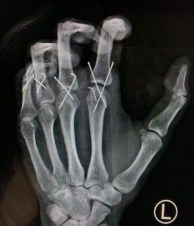

黎医生手术团队为李伟紧急进行了“左手2-5指清创再植术”。术中先清创,予克氏针固定骨折断端及关节,修复肌腱韧带断端,高倍显微镜下吻合左手2-5指血管神经,术中松止血带,血管通血良好。手术顺利,全程6小时。

术后即刻